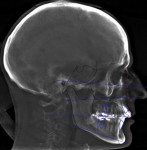

In the case presented, a 59-year-old male patient had severe OSA (AHI 45), decreased posterior airway space, and concomitant maxillofacial skeletal deformities (Angle class II malocclusion, maxillary and mandibular retrognathia, transverse maxillary hypoplasia, and transverse mandibular hypoplasia) (Figure 1 through Figure 4). Orthognathic surgical planning included tracings of a reconstructed lateral cephalogram to estimate postsurgical esthetic changes after advancements of 8 mm, 10 mm, and 12 mm (Figure 5). It is important to note that facial esthetics may change significantly, and this must be discussed in detail with the patient.